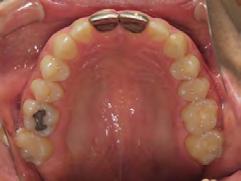

Palatal mini-implants were placed by a periodontist, followed by placement of the rapid palatal expander (RPE) and bonding of the mandibular arch with self-ligating Damon clear braces. Patient had SARPE surgery performed by the oral surgeon three weeks later (Figure 2), and the expander was turned once a day for three weeks (Figure 3). The maxillary arch was then bonded. Both archwires were incremen-

tally upgraded to an 18 x 25 NiTi wire, and the patient was placed on vertical elastics on the right side. With enough space for the tongue, the lateral open bite began to close.

Approximately six months after insertion of the RPE, digital scans were taken for SureSmile custom wires and the patient was scheduled for the SFOT procedure with the oral surgeon. The RPE was removed, SureSmile wires inserted and segmental corticotomies performed, immediately followed by further vertical elastics on the right side (Figure